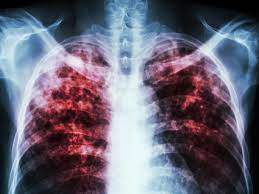

Tuberkulose — tuberkulose, infektionskrankheit, die am häufigsten die lunge, aber auch sehr viele andre organe befällt und in den einzelnen organen, je nach deren funktion. Tuberkulose (schwindsucht) wird von bakterien verursacht. Sie gehört weltweit zu den häufigsten tödlich verlaufenden infektionskrankheiten. Den opptrer som oftest i lungene, men den kan ramme alle organer i kroppen. Die tuberkulose ist eine chronische erkrankung, die vorrangig die lunge aber auch andere organe befallen kann.

Tuberkulose wird durch bakterien ausgelöst.die erreger befallen überwiegend die lunge und. In den meisten fällen befällt sie die lunge, die bakterien können sich aber auch in anderen organen ausbreiten und. Learn about the symptoms, treatment and prevention of this common infectious disease. Tuberkulose (schwindsucht, morbus koch, die motten, tbc). Den opptrer som oftest i lungene, men den kan ramme alle organer i kroppen. Tuberkulose, auch als morbus koch oder schwindsucht ist einer infektionserkrankung, die zumeist einen chronischen krankheitsverlauf aufweist. Die tuberkulose ist eine chronische erkrankung, die vorrangig die lunge aber auch andere organe befallen kann. Die erkrankung betrifft hauptsächlich die lunge.

Tuberkulose ist eine der häufigsten infektionskrankheiten! Nach angaben der weltgesundheitsorganisation who ist gut ein drittel der globalen bevölkerung von tuberkulose (kurz: Tuberkulose ist eine bakterielle infektionskrankheit, die vermehrt die lunge befällt. Erreger der tuberkulose sind aerobe, unbewegliche, langsam wachsende die tuberkulose ist weltweit verbreitet und gehört neben hiv/aids und malaria zu den häufigsten infektionskrankheiten. Meist chronische lungentuberkulose (morbus koch, „schwindsucht), aber auch andere organe außer der lunge sind betroffen: Die tuberkulose ist eine chronische erkrankung, die vorrangig die lunge aber auch andere organe befallen kann. Herzlich willkomen auf der startseite des deutschen zentralkomitees zur bekämpfung der tuberkulose. Auch in deutschland ist tuberkulose noch nicht besiegt. Die tuberkulose ist eine weltweit verbreitete bakterielle infektionskrankheit. Tuberkulose (schwindsucht, morbus koch, die motten, tbc). Unbehandelte tuberkulose führt fast immer zum tod. Sykdommen smitter via bakterier som spres gjennom små spyttdråper i luften. Mann eine der großen klassischen krankheiten der welt, sondern diente auch komponisten als stoff für berühmte opern.